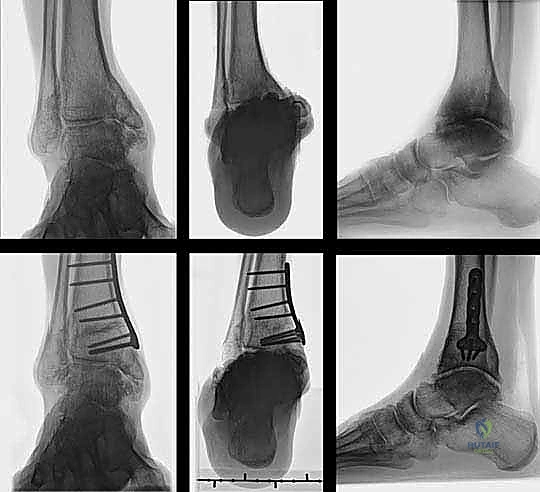

- الأشعة السينية أثناء الوقوف (Weight-Bearing X-rays): هذه هي الخطوة الأهم. لا يمكن تقييم تشوه الكاحل بدقة والمريض مستلقٍ. يجب أخذ صور أشعة طويلة للساقين بالكامل لتحديد "محور التحميل الميكانيكي" وقياس زوايا التشوه بدقة متناهية (مثل زاوية TAS وزاوية TLS).

- قص العظم (Osteotomy): باستخدام منشار جراحي دقيق وموجهات خاصة، يتم قص عظم الظنبوب (وفي بعض الأحيان عظم الشظية أيضاً) بالزاوية التي تم تحديدها مسبقاً في التخطيط الثلاثي الأبعاد.

- تصحيح المحور: يتم فتح أو إغلاق الشق العظمي للوصول إلى المحور الميكانيكي السليم للكاحل. يتم التحقق من ذلك داخل غرفة العمليات باستخدام جهاز الأشعة السينية الفلوروسكوبي (C-arm).

- التثبيت الداخلي (Internal Fixation): بمجرد الوصول للزاوية المثالية، يتم تثبيت العظم في وضعه الجديد بقوة باستخدام شرائح معدنية متطورة (Locking Plates) ومسامير من التيتانيوم. هذا التثبيت القوي يضمن عدم تحرك العظم أثناء فترة الالتئام.